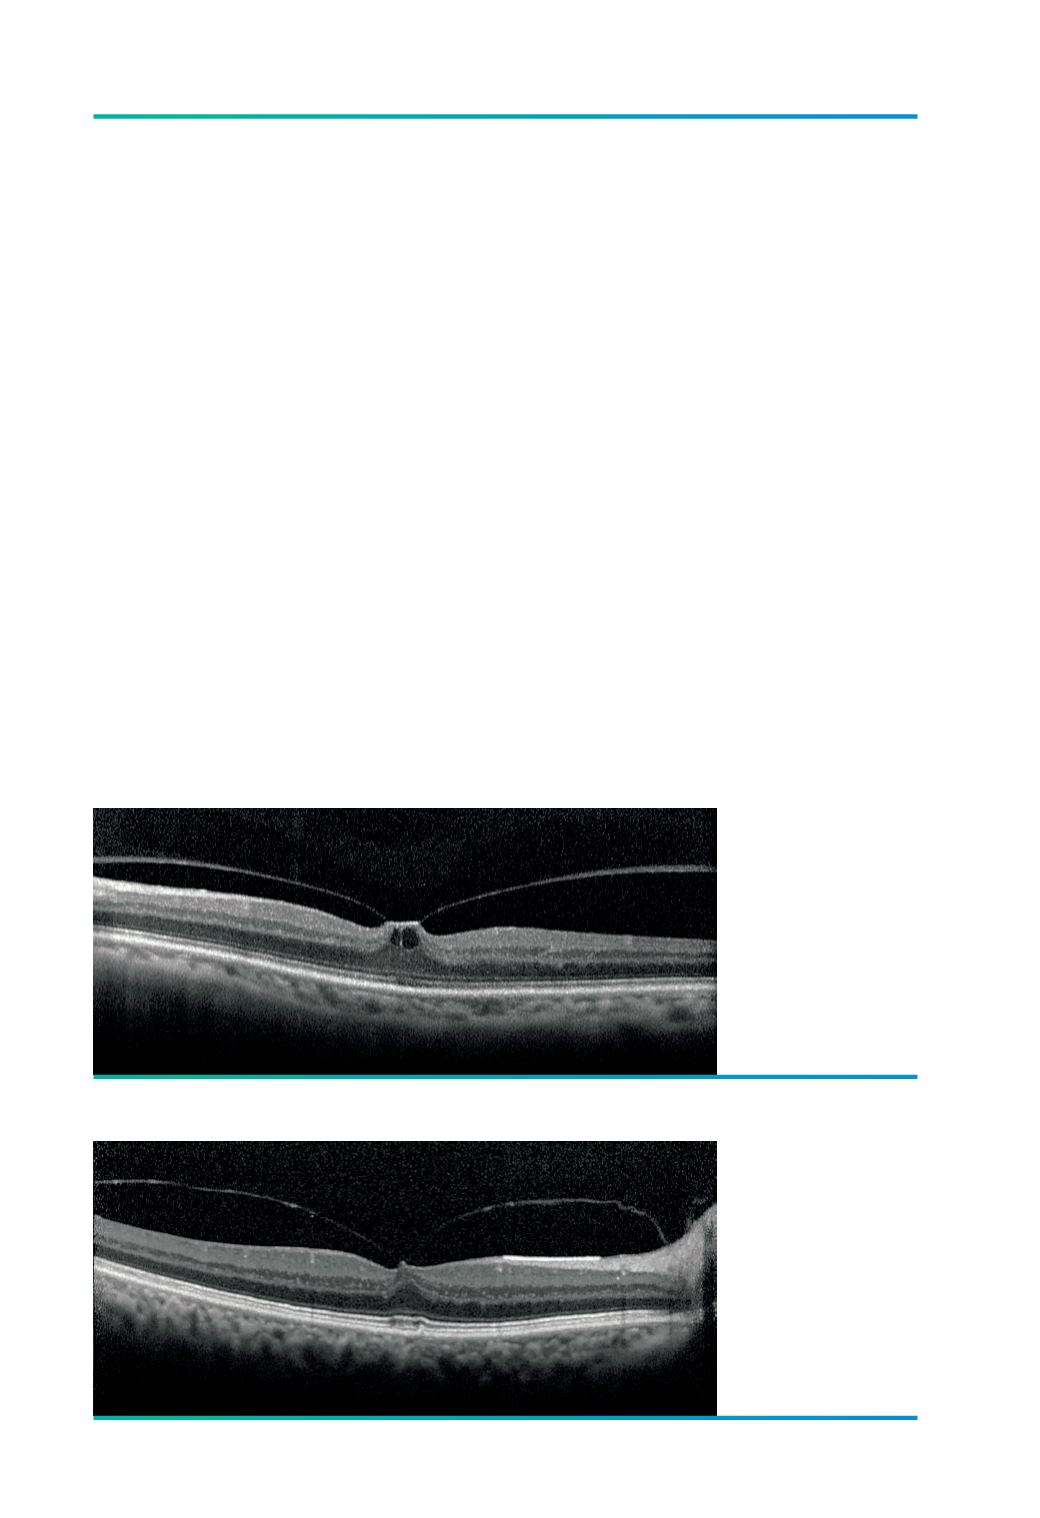

Figura 1.

TVM focal isolada.

Identificam-se

pseudo-quistos

intra-retinianos.

Figura 2.

TVM focal

concomitante

associada a DMI,

onde se observa

ainda uma membrana

epirretiniana e

drusens.